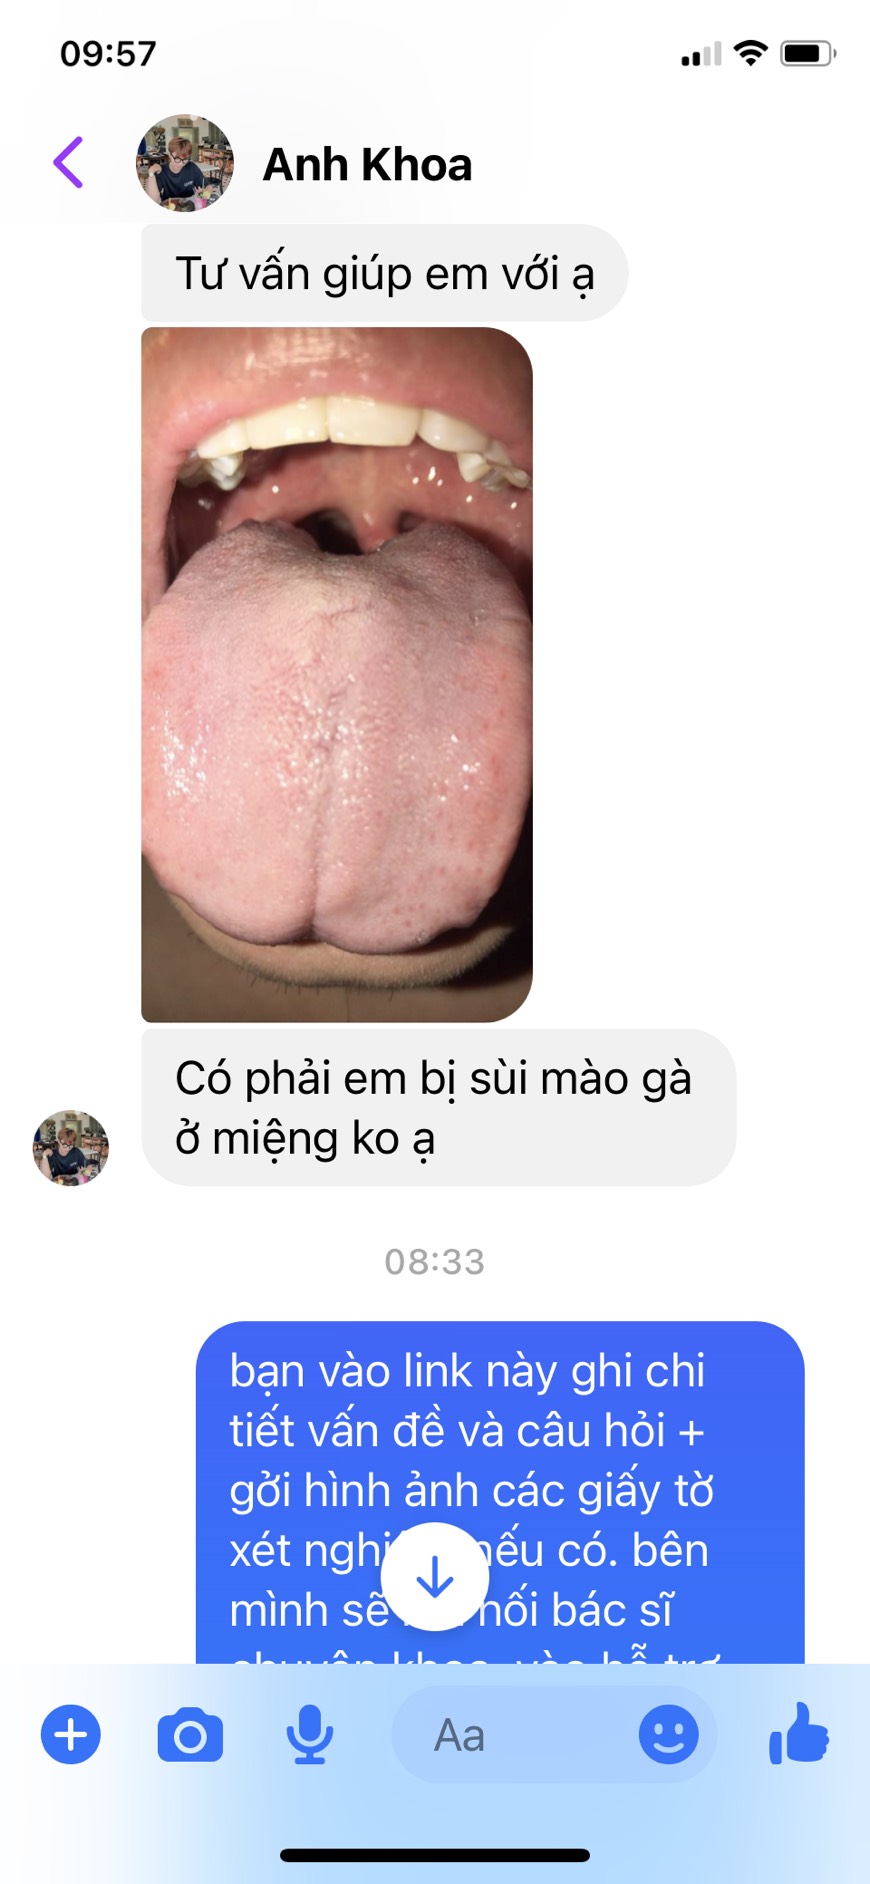

Hỏi đáp trực tiếp với bác sĩ uy tín

Đặt câu hỏi miễn phí

Đặt câu hỏi miễn phí

Hơn 1000 Bác sĩ đang sẵn sàng giúp đỡ bạn